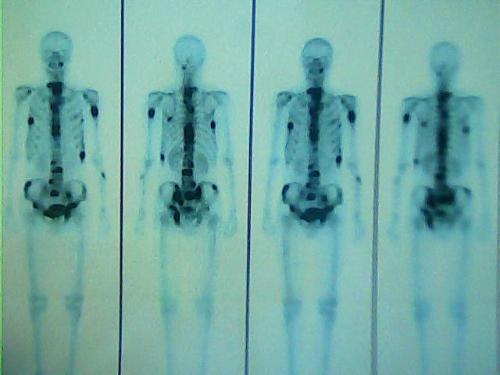

先来说说ECT,所谓ECT,是Emission Computed Tomography的首字母简写,发射单光子计算机断层扫描,是一种利用放射性核素的检查方法,其成像的基本原理是,将放射*药性**物注射入人体,经代谢后在脏器内外或病变部位和正常组织之间形成放射性浓度差异,通过仪器探测这些差异,最后通过计算机进行处理再成像。肿瘤方面,ECT主要用于甲状腺癌、骨骼等部位肿瘤的检查,尤其常用于骨转移性肿瘤的检测,比普通X线拍片可提前3-6个月发现病变。因此,对一些较易发生骨转移的癌症,如乳腺癌、肺癌、前列腺癌、食管癌等,即使没有骨痛,也可做检查,以期早期发现转移灶。由于用于ECT检查的大部分药物都由尿排泄出体外,所以,检查后多饮水以加速药物的排出。